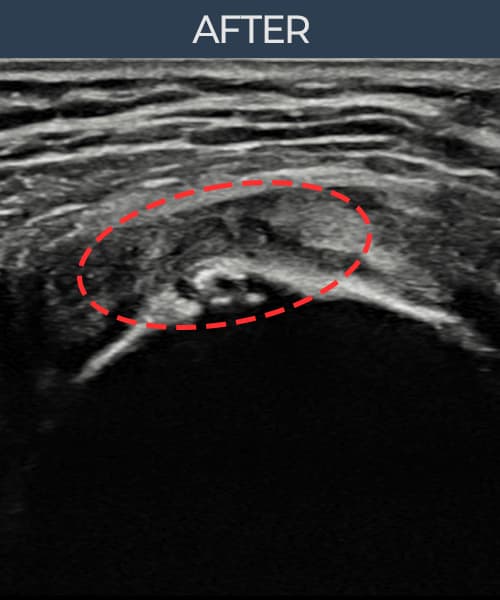

施術後

術前超音波にて腱板 関節面側断裂・肩棘上筋腱のエコー不連続と腱欠損(9mm × 5mm (腱厚の約50%欠損))を確認。術後超音波では断裂部位が再生組織で充填され、腱の連続性回復とエコーパターンの正常化が確認されました。

持続する肩痛で来院された患者様です。超音波検査にて腱板 関節面側断裂(欠損:9mm × 5mm (腱厚の約50%欠損))を確認し、超音波ガイド下で非手術的縫縮術を施行しました。術後は約4〜6週間のブレース装着の後、段階的なリハビリプログラムを実施。経過超音波で腱の連続性回復を確認し、患者様は無事に日常生活へ復帰されました。